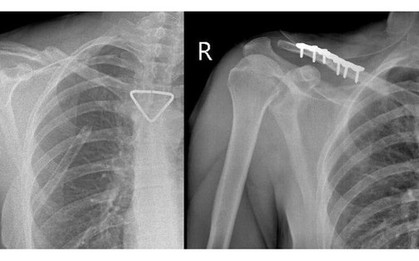

Bác sĩ TP HCM "giành lại" đôi chân cho thầy giáo Campuchia

Vượt quá "giờ vàng", các bác sĩ ở TPHCM nỗ lực phẫu thuật để hồi sinh chân cho người thầy giáo.